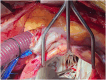

A 53-year-old male individual with chronic severe mitral regurgitation presented with biventricular dysfunction, pulmonary hypertension, and atrial fibrillation. Echocardiography demonstrated a posterior leaflet prolapse with malcoaptation. Mitral valve repair and Maze procedure were performed, revealing absent chordae and direct connection from the anterolateral papillary muscle to the posterior leaflet, consistent with partial mitral arcade. Post bypass, left ventricular dysfunction was addressed by intraaortic balloon pump placement and delayed sternal closure. Post chest closure echocardiography showed no residual mitral regurgitation and restored biventricular function. This case highlights a rare presentation of mitral regurgitation with unique anatomical anomaly, successfully managed with a comprehensive surgical approach.